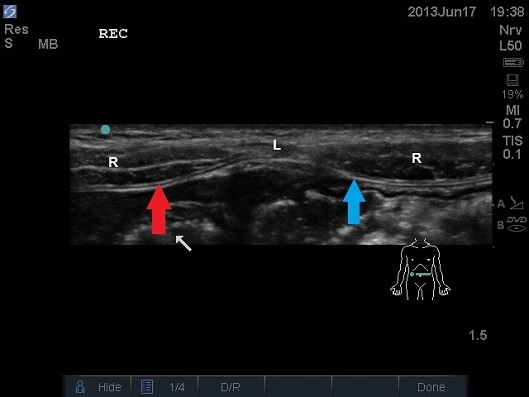

ULTRASOUND OF INFANT ABDOMEN IN TRANSVERSE PLANE. WHITE ARROW – BOWEL, BLUE ARROW FASCIA TRANSVERSALIS AND PERITONEUM, RED ARROW POSTERIOR FASCIA,L – LINEA ALBA, R – RECTUS MUSCLE.

- Move the probe laterally and scan the rectus abdominis muscle in the transverse plane. As the probe is moved laterally the semilunaris (lateral border) is visualised.

- Just lateral to the semilunaris the 3 lateral muscles are seen to come together.

- Deep to the rectus sheath is a continuous hyperechoic line that is the peritoneum, it crosses the midline.